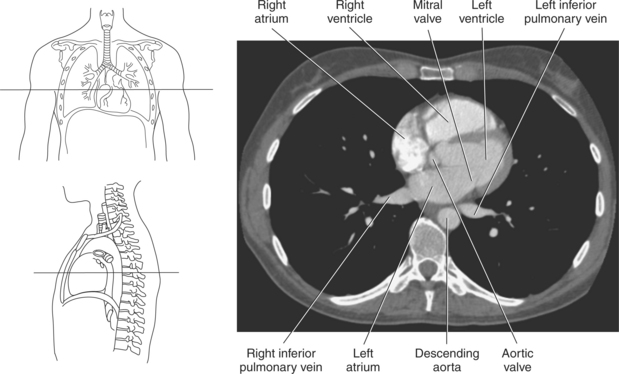

The right atrium forms the right border of the heart and receives deoxygenated blood from the body via the superior and inferior venae cavae and from the coronary sinus and cardiac veins that drain the myocardium. A small muscular embryonic appendage, the right auricle, projects upward and toward the left from the right atrium, covering the root of the aorta (Figure 6.40). The right ventricle lies on the diaphragm and comprises the largest portion of the anterior surface of the heart. It receives deoxygenated blood from the right atrium and forces it into the pulmonary trunk for conveyance to the lungs. Projecting off the inferior surface of the ventricular walls are conical-shaped projections of cardiac muscle called papillary muscles that anchor the cusps of the tricuspid valve to the right ventricle (Figure 6.39). The left atrium lies posterior to the right atrium and is the most posterior surface of the heart. It also has an embryonic appendage, the left auricle, that projects to the left of the pulmonary trunk over the superior surface of the heart. The left atrium receives oxygenated blood directly from the lungs via the four pulmonary veins (two on each side). The left ventricle forms the apex, left border, and most of the inferior surface of the heart. It receives oxygenated blood from the left atrium and pumps it into the aorta for distribution throughout the systemic circuit. The myocardium of the left ventricle is normally three times thicker than that of the right ventricle, reflecting the force necessary to pump blood to the distant sites of the systemic circulation (Figures 6.41 through 6.52). Two papillary muscles project from the ventricular walls to anchor the bicuspid valve to the ventricle (Figures 6.39 and 6.47).

The two atrioventricular valves are found at the entrances to both ventricles and function to prevent backflow of blood between the atria and ventricles during ventricular contraction. These valves have leaflets that are attached to the papillary muscles by thin cords of fibrous tissue called chordae tendineae. The right atrioventricular valve, with three leaflets, is called the tricuspid valve, and the left atrioventricular valve, with two leaflets, is called the bicuspid (mitral) valve (Figures 6.39, 6.43, 6.44, 6.47, and 6.48).

The semilunar valves are located at the junction where the ventricles meet the great vessels, separating the ventricles from the circulatory system. These valves are called semilunar because of their three crescent-shaped cusps and function to prevent the flow of blood back into the ventricles during ventricular relaxation. The pulmonary semilunar valve is located at the juncture of the right ventricle and pulmonary artery, and the aortic semilunar valve lies between the left ventricle and ascending aorta (Figure 6.51 through 6.53).

Blood travels to and from the heart through the great vessels, which include the aorta, pulmonary arteries and veins, and superior and inferior venae cavae (Figures 6.54 and 6.55). The aorta is the largest artery of the body and can be divided into the ascending aorta, aortic arch, and descending aorta. The ascending aorta begins at the base of the left ventricle at the level of the sternal angle, then curves superiorly and posteriorly as the aortic arch over the root of the left lung. The top of the aortic arch is approximately at T3 (Figures 6.56 and 6.57). The arch continues as the descending aorta posterior to the left bronchus and pulmonary trunk, on the left side of the vertebral body of T4 (Figures 6.58 and 6.59). The descending aorta passes slightly anterior and to the left of the vertebral column as it descends through the thoracic and abdominal cavities (Figure 6.60). While in the thoracic cavity, the descending aorta is commonly called the thoracic aorta, and while in the abdominal cavity, it is called the abdominal aorta. The pulmonary trunk is the origin of the right and left pulmonary arteries and lies entirely within the pericardial sac. It arises from the right ventricle and ascends in front of the ascending aorta, courses posteriorly and to the left, where it bifurcates at the level of the sternal angle (T4) into the right and left pulmonary arteries (Figures 6.61 through 6.63). The pulmonary trunk is attached to the aortic arch by a fibrous cord called the ligamentum arteriosum, the remnant of an important fetal blood vessel (ductus arteriosus) that links the pulmonary and systemic circuits during fetal development (Figures 6.54 and 6.61). The right pulmonary artery courses laterally, posterior to the ascending aorta and superior vena cava, and anterior to the esophagus and right mainstem bronchus, to the hilum of the right lung. At the root of the right lung, the right pulmonary artery divides into two branches, with the lower branch supplying the middle and inferior lobes and the upper branch supplying the superior lobe (Figures 6.61 through 6.64). The left pulmonary artery, shorter and smaller than the right, is also the most superior of the pulmonary vessels. It travels horizontally, arching over the left mainstem bronchus, and enters the hilum of the left lung just superior to the left mainstem bronchus (Figures 6.61 through 6.64). Within the lungs, each pulmonary artery descends posterolateral to the main bronchus and divides into lobar and segmental arteries, continuing to branch out and to follow along with the smallest divisions of the bronchial tree (Figures 6.61 and 6.64). Located inferior to the pulmonary arteries are the four pulmonary veins, two each (superior and inferior) extending from each lung to enter the left atrium (Figures 6.54, 6.55, 6.61, and 6.64 through 6.68). They commence in a capillary network along the walls of the alveoli, where they are continuous with the capillaries of the pulmonary arteries. The venous capillaries merge to form small vessels that unite successively to eventually form a single trunk for each lobe: three for the right and two for the left lung. Frequently the trunk from the middle lobe of the right lung unites with the trunk from the upper lobe, forming just two trunks on the right side prior to entering the left atrium. The right superior pulmonary vein collects blood from the upper lobe segments of the right lung and passes anterior and inferior to the right pulmonary artery, behind the superior vena cava. The right inferior pulmonary vein receives blood from the right lower lobes of the lung and crosses behind the right atrium to the left atrium (Figures 6.61 and 6.69 through 6.71). The left superior pulmonary vein receives blood from the left upper lobe of the left lung and courses anterior and inferior to the left main bronchus as it enters the left atrium. The left inferior pulmonary vein drains the inferior lobe of the left lung and passes toward the left atrium anterior to the bronchi (Figures 6.61 and 6.72 through 6.74). The pulmonary veins course more horizontally than the pulmonary arteries and are ultimately oriented toward the left atrium. At the root of the lungs, the pulmonary veins are anterior to the pulmonary arteries, which are anterior to the bronchus. While within the lungs, the branches of the pulmonary arteries are anterior to the bronchi, which are anterior to the pulmonary veins. The superior and inferior venae cavae are the largest veins of the body. The superior vena cava is formed by the junction of the brachiocephalic veins, posterior to the right first costal cartilage, and carries blood from the thorax, upper limbs, head, and neck (Figure 6.24). As it travels inferiorly, it is located posterior and lateral to the ascending aorta before entering the upper portion of the right atrium (Figures 6.54 through 6.59). The inferior vena cava is formed by the junction of the common iliac veins in the pelvis and ascends the abdomen to the right of the abdominal aorta and anterior to the vertebral column. It passes through the caval hiatus of the diaphragm and almost immediately enters the inferior portion of the right atrium (Figures 6.75 and 6.76).